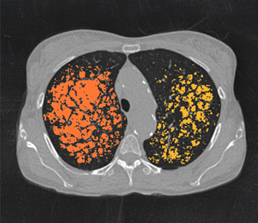

Quantitative assessment

Emphysema severity

Quantitative assessment

Trapped air / Hyperinflation